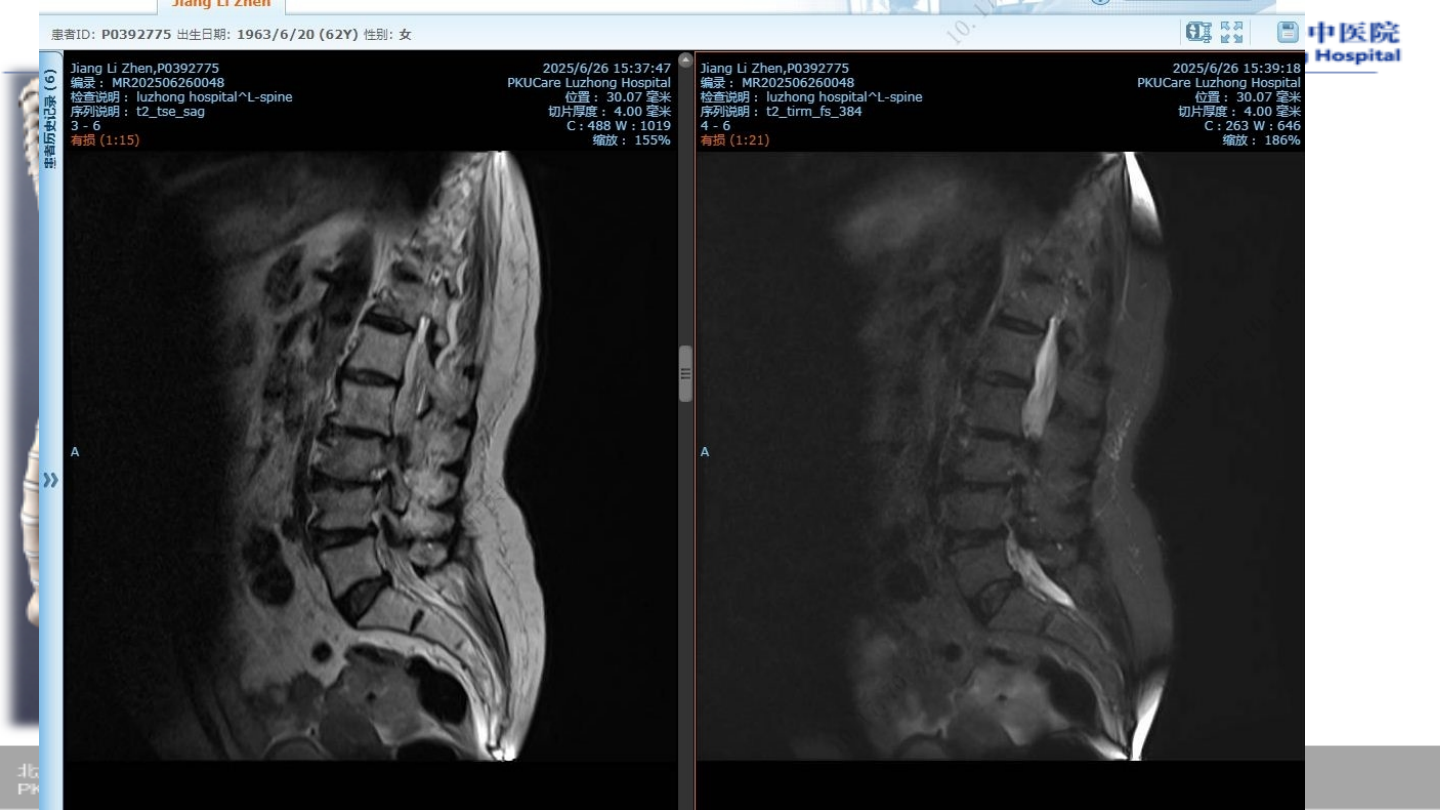

术前腰椎

MRI